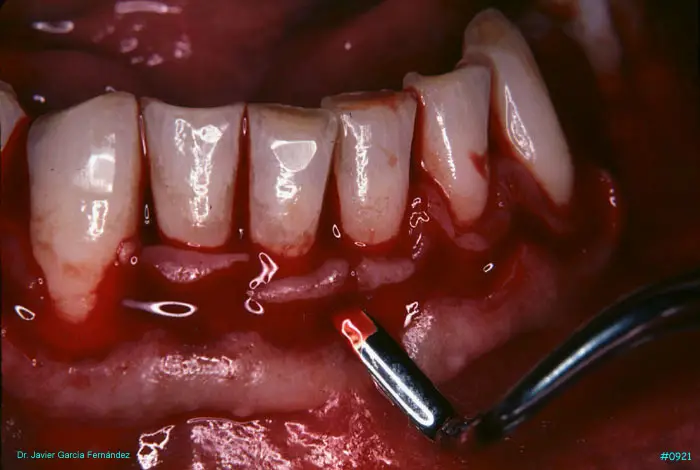

Atlas of Surgical Techniques in Periodontics. Chapter III. Atlas de Técnicas Quirúrgicas en Periodoncia